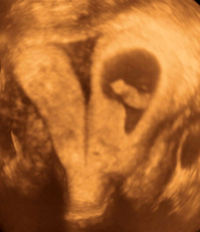

Myelomeningocele high resolution ultrasound.

- Fetal brain and spine anomalies including Spina Bifida, Fetal Ventriculomegaly, Dandy-Walker Malformation, and Agenesis of the Corpus Callosum.

UCSF doctors in ultrasound are also expert in fetal thoracic and abdominal pathologies, including gastroschisis, omphalocele, lung sequestration, and cystic adenomatoid malformation (congenital pulmonary airway malformation) and congenital high airway obstruction (CHAOS). We assist in fetal operations for these anomalies by providing guidance for radiofrequency ablation, laser ablation for Twin-Twin Transfusion Syndrome, fetal blood transfusions, fetal lung mass resections, tracheal balloon placement and fetal surgery for Spina Bifida. (Open myelomeningocele)

Further attesting to our expertise in fetal imaging, UCSF is one of the three centers that performed the prenatal imaging for a recently published New England Journal of Medicine article on prenatal surgery for myelomeningocele.